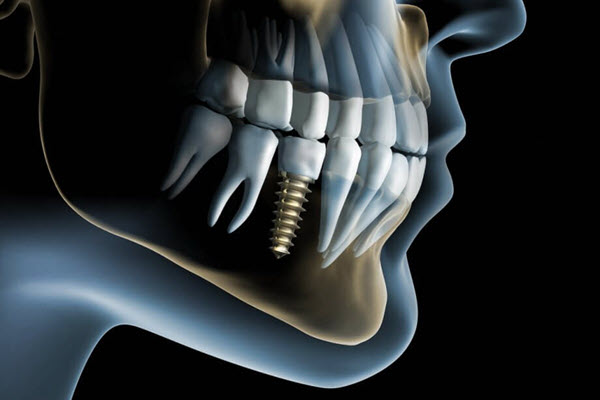

The dental practice, which opened in 2014 and specializes in minimally invasive biomimetic dentistry, now offers affordable implants that function and feel like natural teeth. In fact, you will pay far less here than at most dentists in Auckland - which may seem surprising since the clinic is gleaming and outfitted with the latest technology.

Natural Smile Dental St Heliers, led by Dr Dave Richards, now provides implants that will preserve the health of adjacent teeth - since there is no need for any bridgework - while allowing you the natural comfort of an evenly distributed bite. Plus, you save around $2,000!

The implant procedure can be initiated after Dr Richards and you together review the 3-D imagery and agree on the subsequent steps. Depending on factors such as the state of the tooth being replaced and the surrounding tissue, the implant may be placed in your jaw at the same time as removing the defective tooth - or it may be surgically placed separately.

After the implant has been placed, there is typically a three to six-month recovery time. For a few weeks, a healing cap is placed on top of the implant. The healing cap will then be removed and replaced with an abutment - which is what the tooth-like crown will be placed over for a secure hold.

Natural Smile’s dental restoration process is especially accurate due to the 3D printing technology and oral scanning enabled CAD/CAM tools. The customized fit minimizes the need for repairs or adjustments while ensuring greater comfort and fewer future visits.